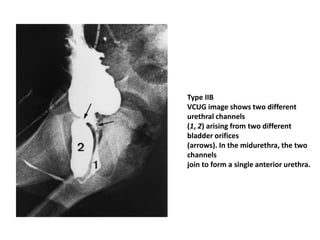

• Urethral duplication can be classified into

three types using Effmann’s classification.

– In type I, there is partial duplication of the

urethra.

– In type II, there is complete duplication of the

– Type III urethral duplication consists of complete

duplication of the urethra and bladder

Type IIB

VCUG image shows two different

urethral channels

(1, 2) arising from two different

bladder orifices

(arrows). In the midurethra, the two

channels

join to form a single anterior urethra.